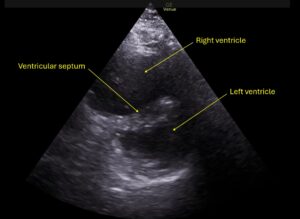

Wolff A, et al. Right atrial thrombosis. Parasternal short US 2, annotated

Wolff A et al. Right atrial thrombosis. Parasternal short US 2 annotated